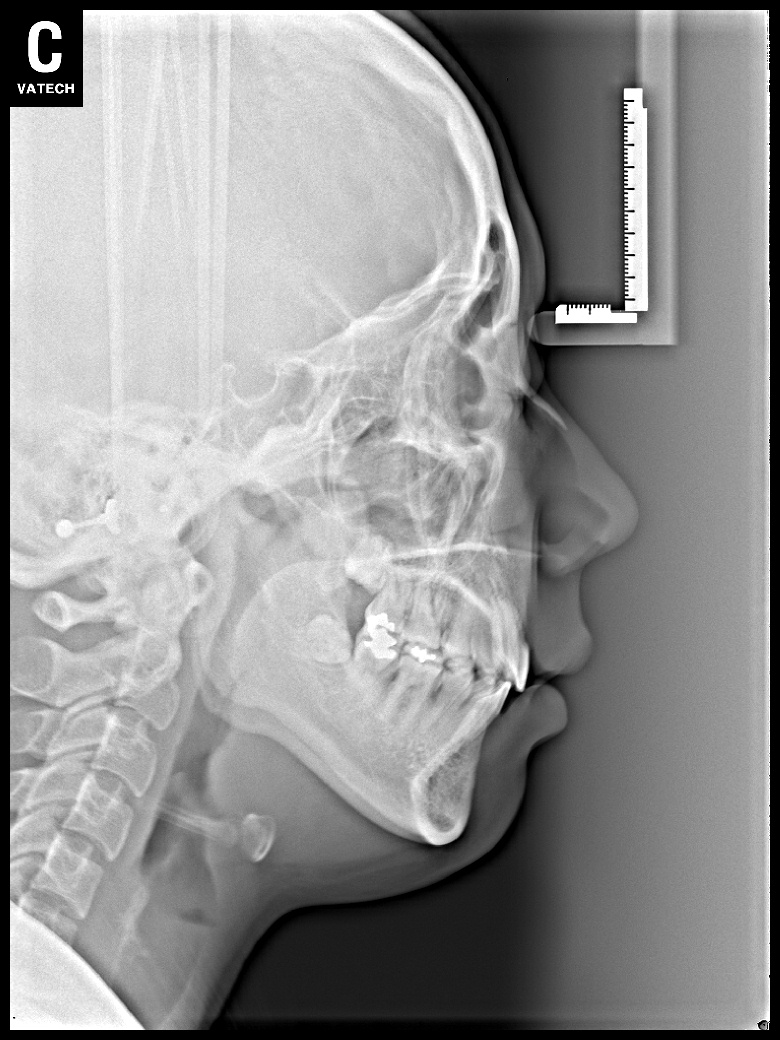

치료 전 사진입니다.